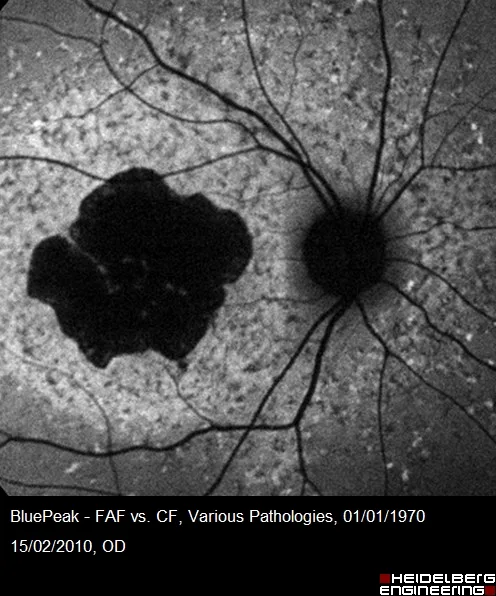

Système de Positionnement Anatomique (APS) : Deux yeux avec des axes « Fovea – Centre du BMO » très différents (A et B).

L’orientation des scans de l’OCT SPECTRALIS s’aligne automatiquement sur l’axe FoBMO individuel.